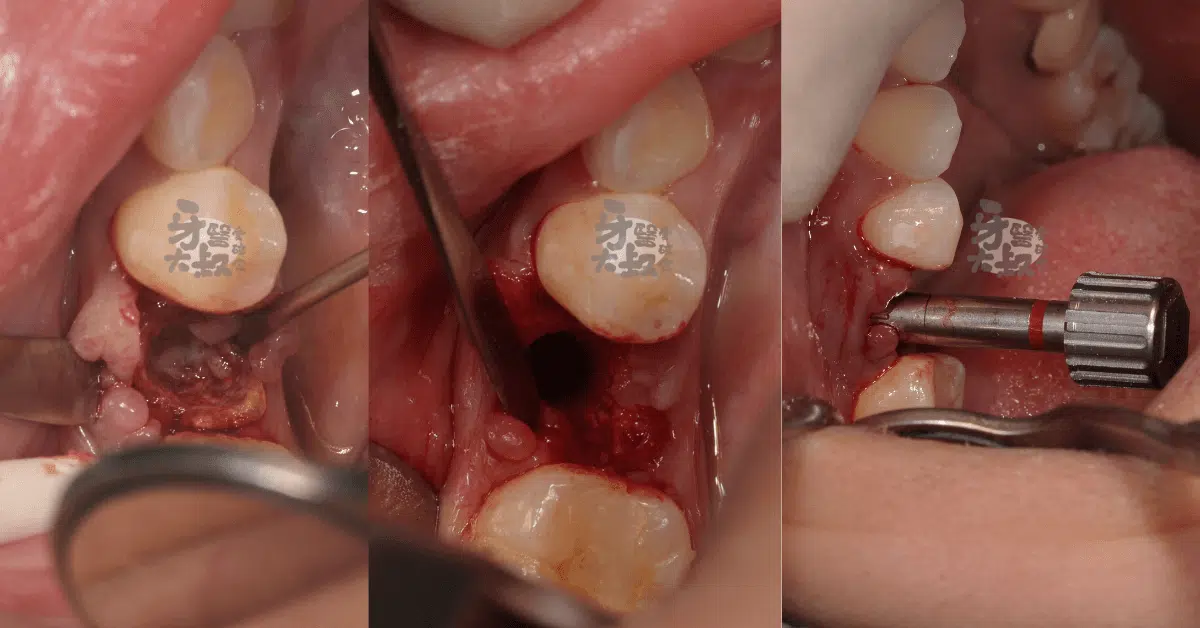

圖左可以看到翻開的牙齦中隱約有一個殘存的牙根,即拔即植的其中一個重點就是要微創拔牙,在不破壞周圍骨頭的情況下小心地將牙根拔除。

圖中為牙根拔除後,這時候大叔會先判斷周圍骨頭的狀況,尤其是確認頰側的骨壁是否完整來決定待會要補的骨粉份量。由於植入的人工牙根直徑通常會小於拔牙窩,所以即使沒什麼缺損的骨壁還是會盡量塞入骨粉來避免骨頭變化太多喔。

圖右為植體植入後。